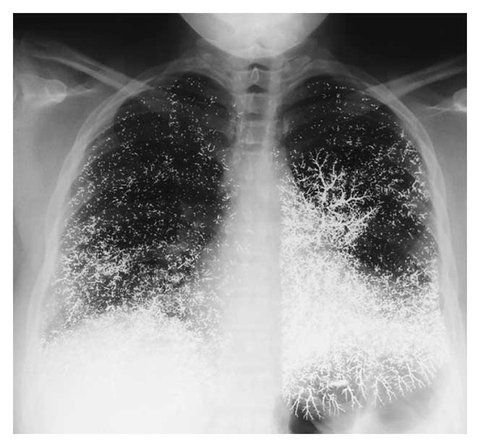

수은먹고 자살 시도한 여자의 엑스레이

ㄷㄷ

와 진짜 무슨 눈꽃같기도 하고 오싹하네

눈의꽂같다

수은을 식도로 넘겼는데 폐로 가? ---------- http://pann.nate.com/talk/325117221